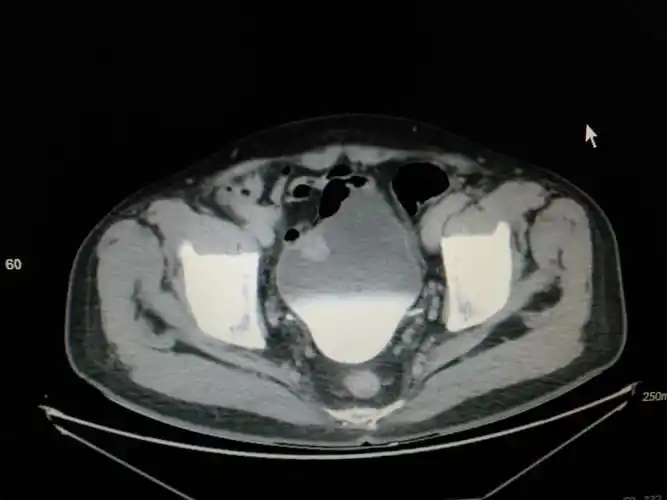

"针状电极t2期膀胱肿瘤剜除术"一例分享——术者:兰大二院尚攀峰